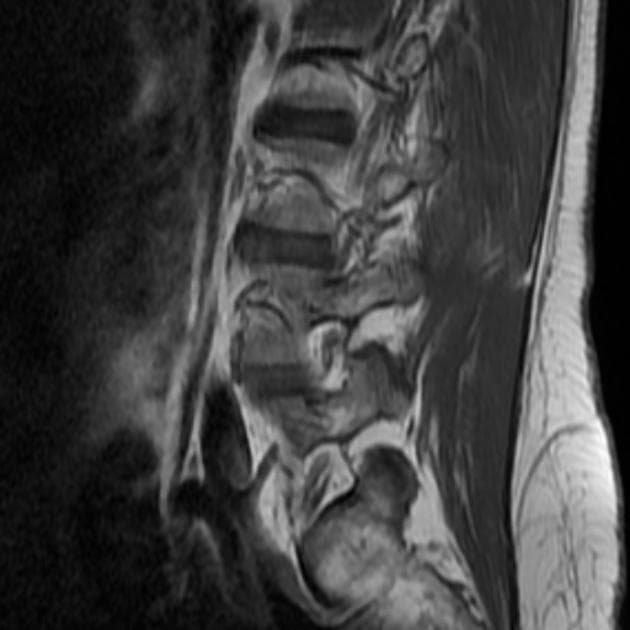

Dày đáng kể vùng nối nội mạc - cơ tử cung (endo-myometrial junctional zone), chủ yếu ở thành tử cung sau, phù hợp với lạc nội mạc tử cung trong cơ (adenomyosis).

Tử cung, cả hai buồng trứng và trực tràng bị kéo sát lại gần nhau do các dải dính co thắt / xơ hóa, dẫn đến "dấu hiệu lá cỏ ba lá (cloverleaf sign)" – một hình ảnh mới được mô tả trong lạc nội mạc tử cung xâm lấn sâu (deep infiltrating endometriosis).

- Các hình ảnh cộng hưởng từ (MRI) thấy phù hợp nhất với lạc nội mạc tử cung xâm lấn sâu, kèm theo lạc nội mạc buồng trứng hai bên và adenomyosis tử cung.